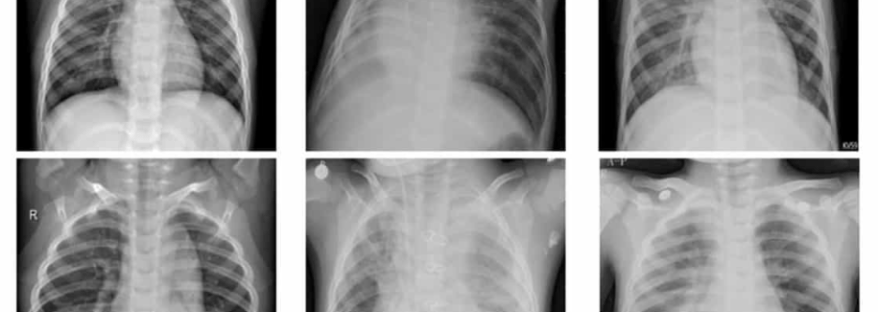

Pneumonia is an infection that causes the air sacs in the lungs to fill up with fluid or pus, which makes it harder to breathe. The most common symptoms are cough that may be dry or produce phlegm, fever, chills, and fatigue. Other symptoms may include nausea, vomiting, diarrhoea, and pain in the chest. and shortness of breath. Signs that indicate a more severe infection are shortness of breath, confusion, decreased urination, and light-headedness.

The more severe symptoms of COVD-19, such as high fever, severe cough, and shortness of breath, usually mean significant lung involvement. The lungs can be damaged by overwhelming COVID-19 viral infection, severe inflammation, and/or a secondary bacterial pneumonia. COVID-19 can lead to long lasting lung damage.

COVID-19-aquired pneumonia can cause lasting lung damage. While most people who recover from pneumonia tend not to suffer from any serious long-term lung damage, pneumonia caused by the coronavirus is often more severe and may result in long-term symptoms or a form of lung failure called acute respiratory distress syndrome (ARDS). Patients suffering from ARDS may be put on a ventilator while in the hospital to help oxygen circulate throughout the body. ARDS may cause pulmonary scarring and can be fatal.